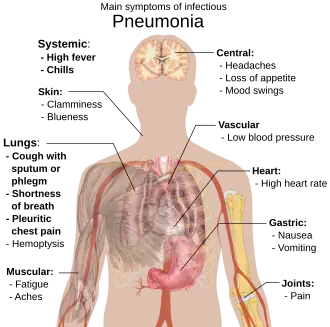

Signs and symptoms

Common symptoms

- Coughing which produces greenish or yellow sputum

- A high fever, accompanied by sweating, chills and shivering

- Sharp, stabbing chest pains

- Rapid, shallow, often painful breathing

Less-common symptoms

- Coughing up blood (hemoptysis)

- Headaches, including migraines

- Loss of appetite

- Excessive fatigue

- Bluish skin (cyanosis)

- Nausea

- Vomiting

- Diarrhea

- Joint pain (arthralgia)

- Muscle aches (myalgia)

- Rapid heartbeat

- Dizziness or lightheadedness